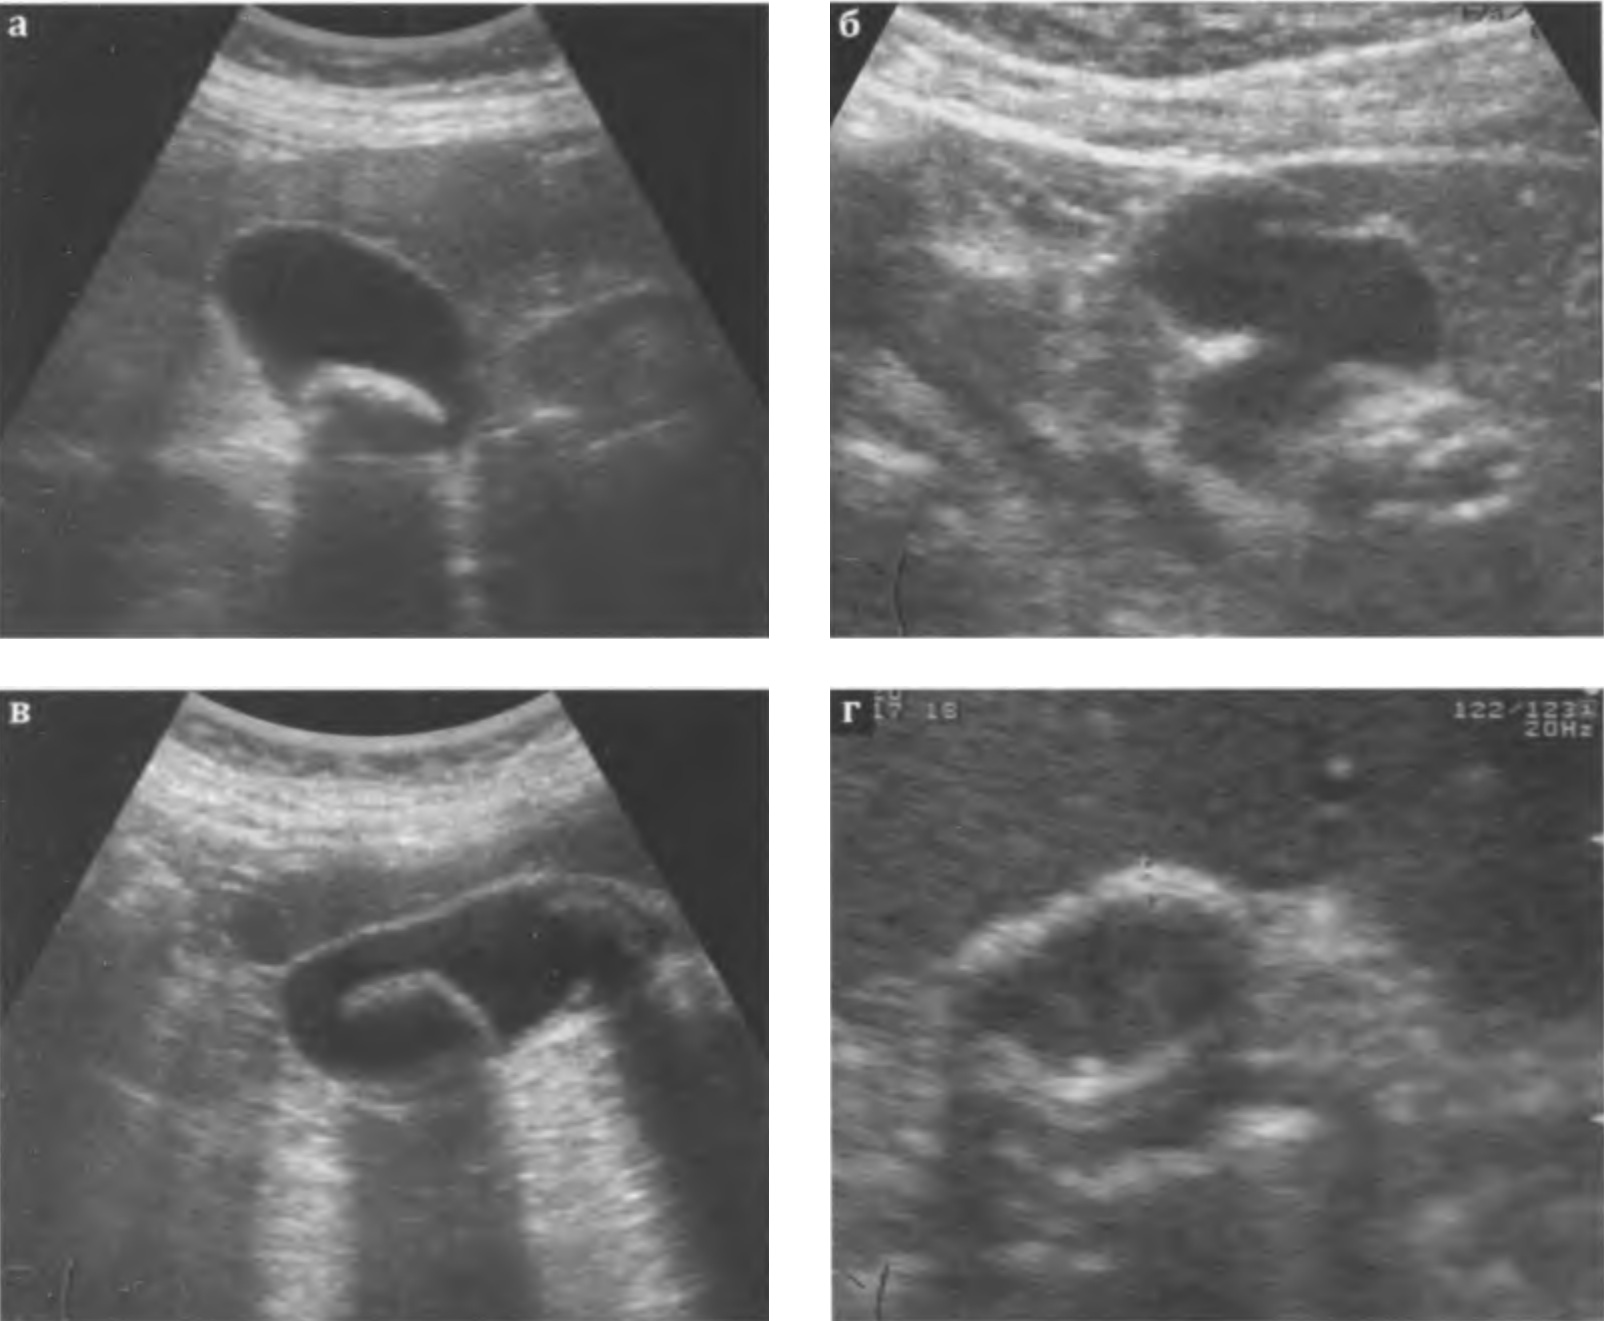

Хронический холецистит. Ультразвуковые признаки хронического воспаления желчного пузыря не столь очевидны, как признаки острого воспаления. Размеры пузыря могут не изменяться, увеличиваться (при нарушении оттока желчи), уменьшаться (при сморщивании и склерозе стенки). При гипертрофической форме хронического воспаления толщина стенки желчного пузыря в среднем составляет 0,3-0,4 см, а при атрофической форме не превышает 0,1-0,2 см. Эхогенность стенки повышается, часто неравномерно. Контур становится неровным за счет рубцовых изменений. В просвете могут определяться застойная желчь, взвесь, камни (рис. 3.11 а-г). Изменения в окружающих тканях и реакция лимфатической системы не выражены. Исходом хронического рецидивирующего холецистита может быть сморщивание пузыря и его склероз: размеры желчного пузыря уменьшены, стенка значительно утолщена, неравномерно повышенной эхогенности, полость приобретает щелевидную форму, в просвете может определяться сгущенная желчь и конкременты.

Рис. 3.11 а, б, в ,г. Хронический калькулезный холецистит: а,б,в - стенка желчного пузыря повышенной эхогенности, в просвете лоцируются конкременты; г - сморщенный желчный пузырь; стенка значительно утолщена (+...+), неравномерно повышенной эхогенности, просвет уменьшен, в просвете - сгущенная желчь и конкременты.